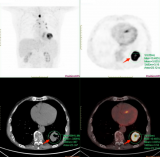

靶向MC1R的Ac-225治疗性核药完成首例患者给药,Alpha-9 Oncology的黑色素瘤诊疗一体化项目取得重要进展

2025年12月4日,临床阶段的放射性药物研发公司Alpha-9 Oncology宣布,已启动一项I期研究,并完成首例患者给药。该研究旨在评估A9-3408的安全性、剂量学及剂量递增情况,这是一种新型靶向黑色素皮质素1受体(MC1R)的Ac-225核素药物,用于治疗经标准疗法治疗后病情进展的MC1R阳性黑色素瘤患者。这一里程碑式的进展推动了Alpha-9的黑色素瘤项目。该项目于去年随着A9-3202的启动而首次进入临床阶段,A9-3202是一种基于Ga-68的显像剂,用于评估MC1R的表... 2025-12-06 核医药放射性药物